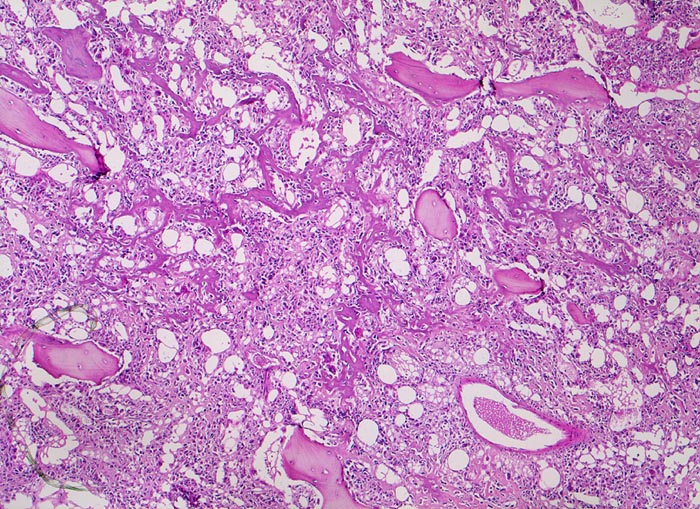

Osteosarkom

Knochen, Femur

Die breiten ursprünglichen lamellären Knochenbälkchen sind weitgehend erhalten. Das von den atypischen Tumorzellen gebildete unregelmässige und fein vernetzte Tumorosteoid liegt in den Markräumen und lagert sich teilweise dem ortsständigen Knochen an.

16 jähriger Jugendlicher mit seit mehreren Wochen bestehenden belastungsunabhängigen Schmerzen im distalen Femur rechts oberhalb des Knies (Metaphyse). Im Röntgenbild irreguläre Verdichtung, zum Teil auch Aufhellung der ursprünglichen Knochenstruktur mit Zerstörung der Corticalis und spiculaartige (=sonnenstrahlenähnliche) Periostreaktion. Im Serum erhöhte alkalische Phosphatase.

Histologie

50